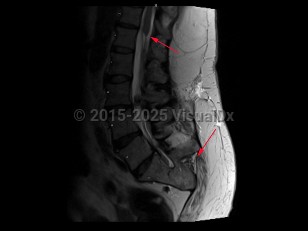

Caudal regression syndrome in Infant/Neonate

Congenital abnormality characterized by malformation or absence of the sacrum, usually with associated spinal dysraphism and tethered cord. Presentation can range from mild to life-threatening. It may be an isolated defect or can be found as part of associated syndromes, such as the VACTERL association (vertebral defects, anal atresia, cardiac defects, tracheo-esophageal abnormalities, renal and radial abnormalities, and limb abnormalities).

Other characteristics include narrow hips, hypoplastic gluteal muscles, short intergluteal cleft, sacral dimple, lower limb flexion contractures, clubfeet, and leg atrophy. Neurological abnormalities such as poorly controlled urinary and bowel function are often observed. Most commonly seen in infants born to birthing parents with diabetes. Treatment is symptomatic.